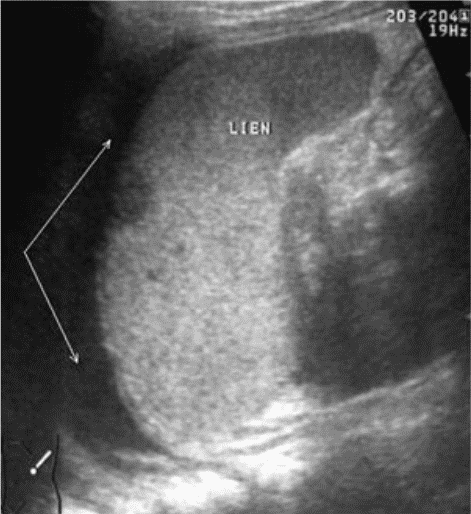

Фрагментация (отрыв полюса) селезенки представляет, по сути, частный вариант чрескапсульного разрыва с полным разобщением фрагментов органа. Наряду с раздельной визуализацией фрагментов выявляются линии разрывов и вышеописанные косвенные признаки, характерные для данного вида повреждений (рис. 10).

Рис. 10. Эхограмма полного поперечного разрыва селезенки. Линия разрыва указана стрелками.